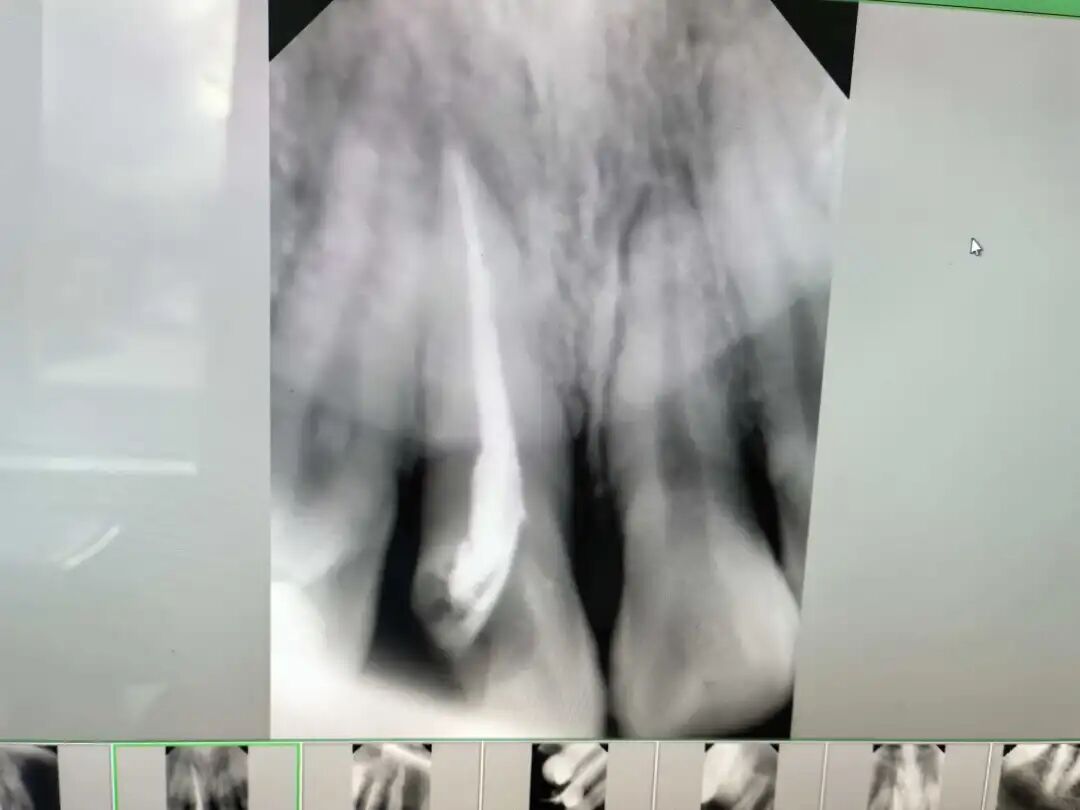

前几日,小美因右上前牙剧烈疼痛,在家人的陪伴下来到医院口腔科。接诊医生经过检查,发现这颗门牙因深度龋坏已伤及牙髓,引发了急性牙髓炎,这正是疼痛的来源。

医生向小美和家属解释了病情,并制定了第一步处理方案——根管治疗。这是一种通过清除牙齿内部感染的牙髓组织,进行彻底清理和填充,从而消除疼痛、阻止炎症继续发展的方法,可以帮助患者保留住自然牙。在医生的操作下,小美的牙痛很快得到缓解。